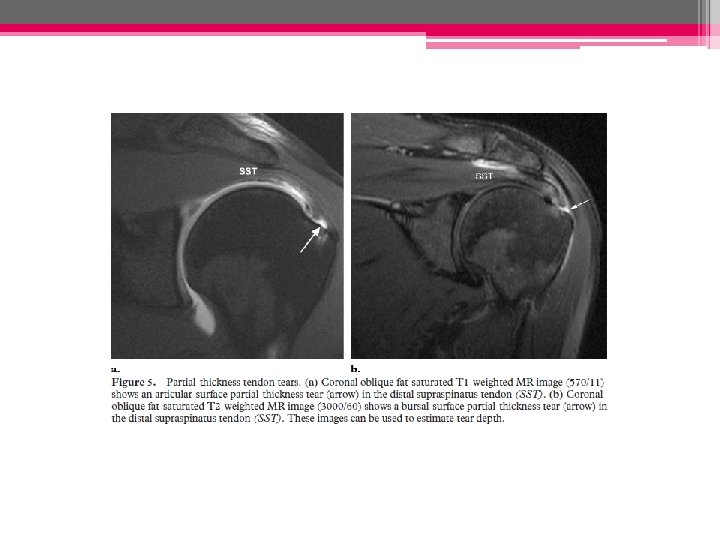

Variétés des ruptures: • Rupture non transfixiante (ou partielle) - n’intéresse qu’une partie de l’épaisseur du tendon - ne crée pas de communication entre la BSAD et la cavité articulaire gléno-humérale - affecte essentiellement la face articulaire de la coiffe C A. Rupture face profonde. B. Rupture face superficielle. C. Rupture intratendineuse.

• Rupture partielle (non transfixiante): - Zone hypoéchogène ++ hyperéchogène entourée d’une zone hypo hyper - Face articulaire (profonde)/bursale (superficielle)/ intra-tendineuse

◊ Ruptures partielles profondes

◊ Ruptures partielles superficielles:

IRM: - Hypersignal tendineux modéré en DP, intense (de type liquidien) en pondération T 2 - Dégénerescence graisseuse et amyotrophie: pondération T 1 - NB: pfs réaction oedémateuse de la MO adjacente au tendon # pathologie tumorale, septique ou rhumatismale